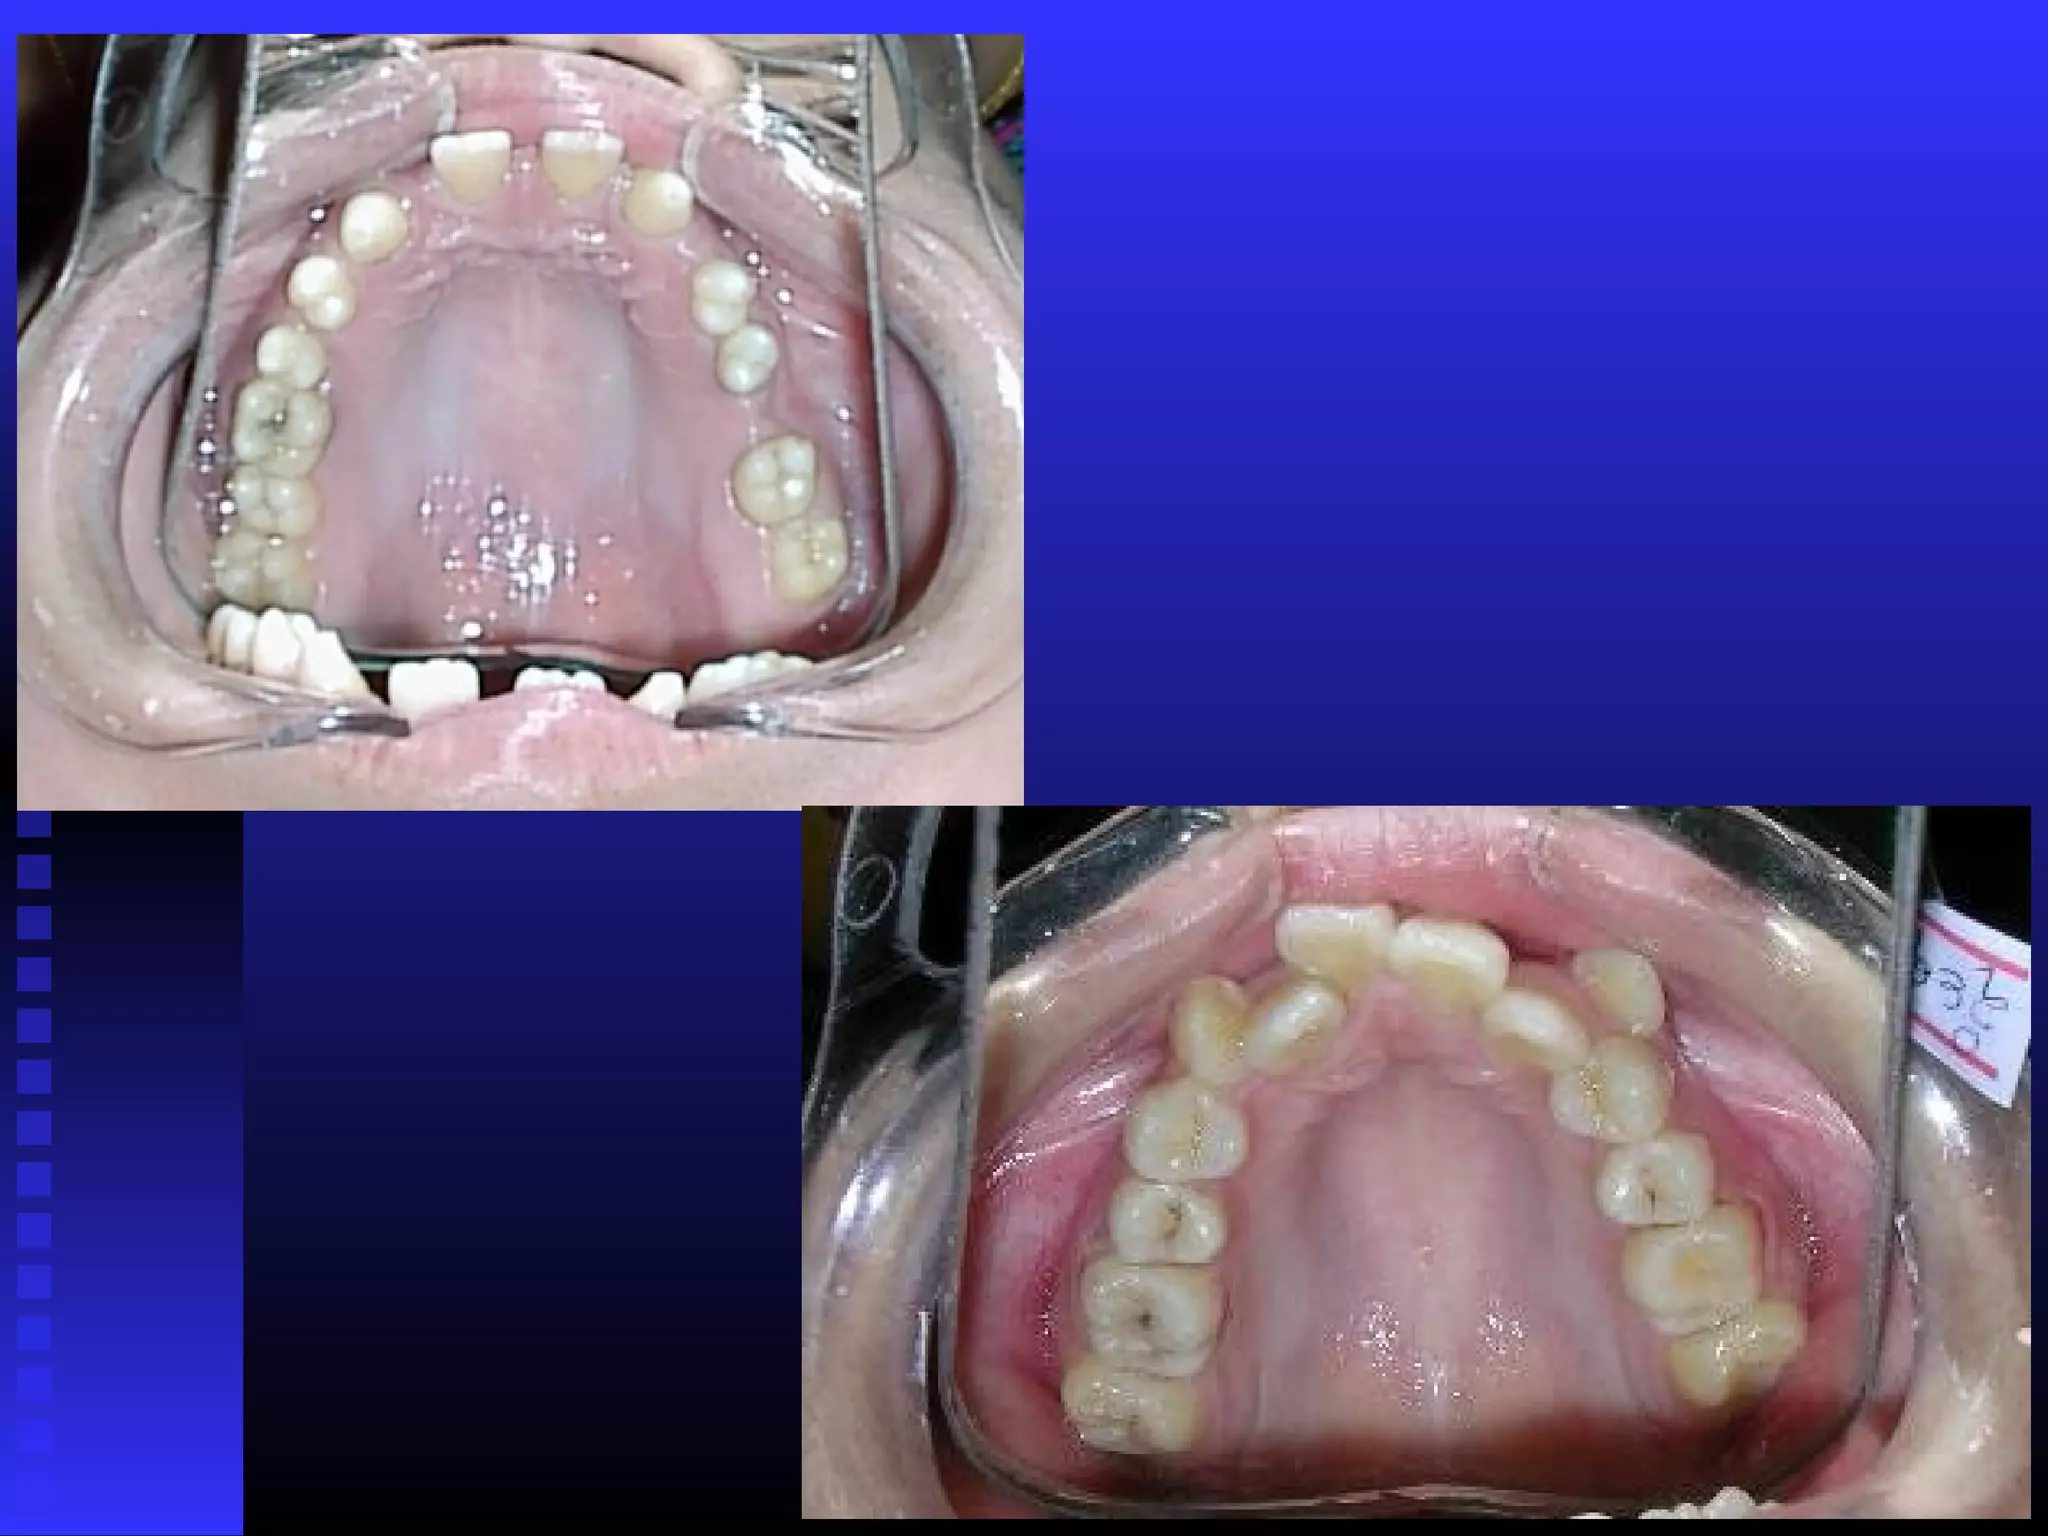

• Most class I malocclusions are presenting with crowding due to

tooth size arch size discrepancy.

• Crowding may be superimposed with local factors such as early

loss ,

supernumerary.

Class I Malocclusions